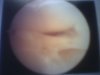

okay i got pics of knee and soon ill post a lot of them cuz i have total of 21 pictures so please bear with me alright? hehe

okay first pic looks like my lignament and it has damaged tissues around and 2nd one look healthy enough to me however there was a comment abt that and i cant even read it... to me it look like bucklet vendle menisus tear... 3rd and 4th picture u can see clearly of torn muscles. they look like they just went through paper shredder. the comment under 3rd and 4th pic says something like degenereture menisure but i have no idea what it meant?!?

okay first pic looks like my lignament and it has damaged tissues around and 2nd one look healthy enough to me however there was a comment abt that and i cant even read it... to me it look like bucklet vendle menisus tear... 3rd and 4th picture u can see clearly of torn muscles. they look like they just went through paper shredder. the comment under 3rd and 4th pic says something like degenereture menisure but i have no idea what it meant?!?